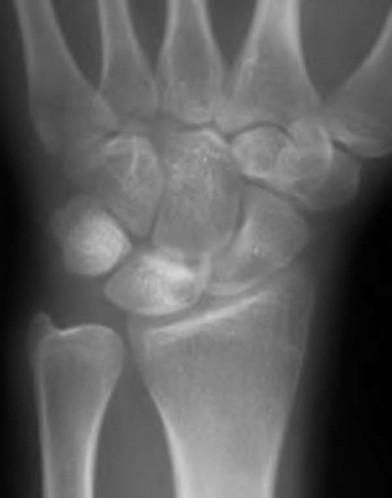

A 35-year-old woman reports wrist pain after a fall onto an outstretched hand. On exam, she has focal tenderness over the wrist snuffbox. A radiograph and CT image are shown in Figures A and B. What is the proper treatment of her injury?